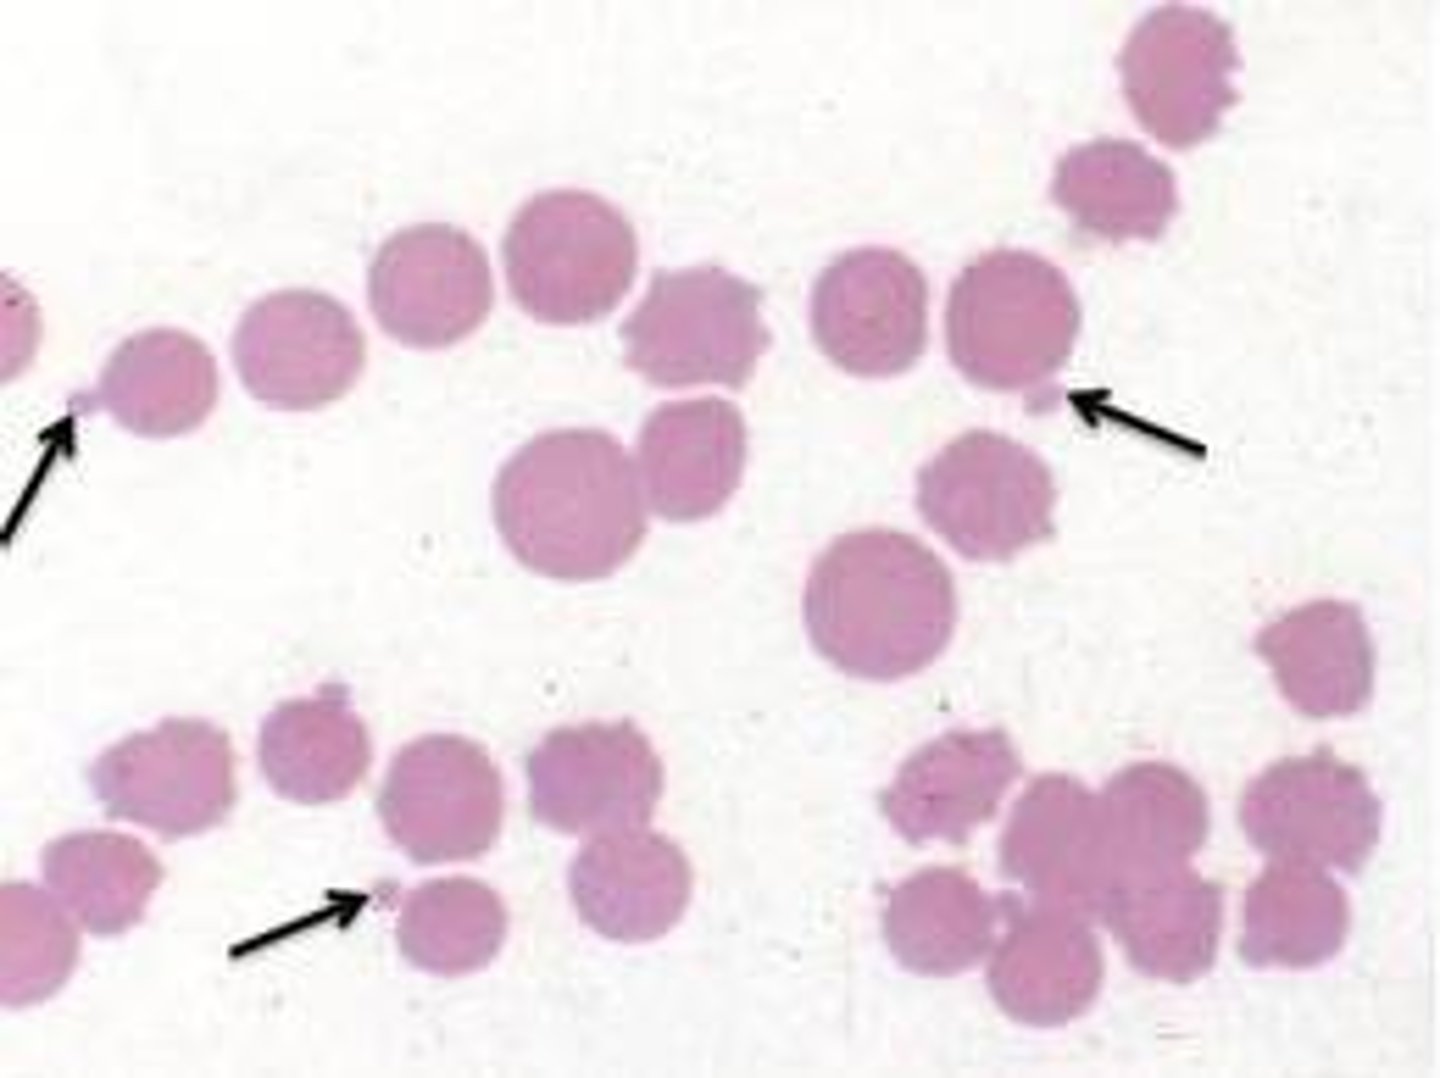

Howell-jolly body

MAMMAL

small basophilic dot typically on the periphery of the RBC